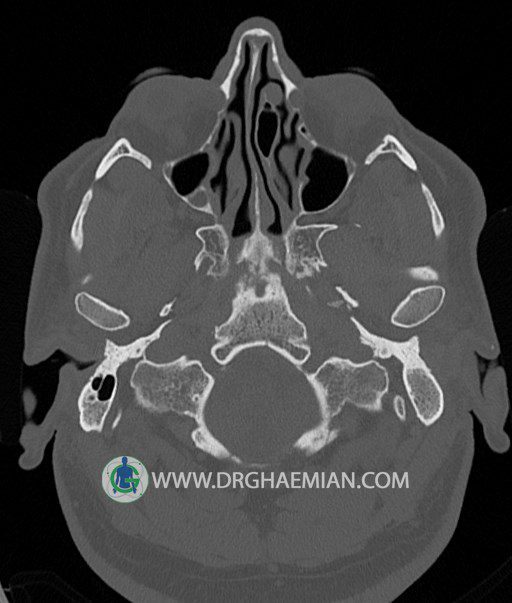

سی تی اسکن گوش داخلی به رادیولوژیست اجازه می دهد تا سطوح مختلف، یا اسلایس هایی از استخوان های که از جمجه به گوش می روند را از طریق امواج ایکس چرخشی مشاهده کند. در این کیس اودیت مدیا، ماستوئیدیت مزمن، اوتیت خارجی، انحراف سپتوم بینی، کونکا بولوزا و افزایش ضخامت سینوس ها مشاهده می شود.

در HRCT از استخوان تمپورال با مقاطع آگزيال ، ساژيتال و کرونال ظريف ( 0.6 mm ) :

– نماي کوکلهآي دو طرف با 2.5 دور گردش مجرا

– نماي cochlear aqueduct

– نماي semicircular canal خلفي ، لترال ، فوقاني و وستيبول

– استخوانچه هاي گوش داخلي شامل malleus ، incus و stapes (دنسيتي و رديف استخوانچه ها )

– نماي oval window و round window ، tympanic cavity ، attic و کانال گوش داخلي

– کانال عصب فاشيال و مسير ان از ناحيه کانال گوش داخلي ، geniculate ganglion تا محل خروج ان از stylomastoid foramen

– نماي tympanic membrane ، کانال ICA ، بولب جوگولار دو طرف

– انحراف سپتوم مياني بيني به راست

– کونکا بولوزا در کونکاي مياني چپ و

– افزايش ضخامت مخاطي در سينوس هاي اتموئيد و ماگزيلاري